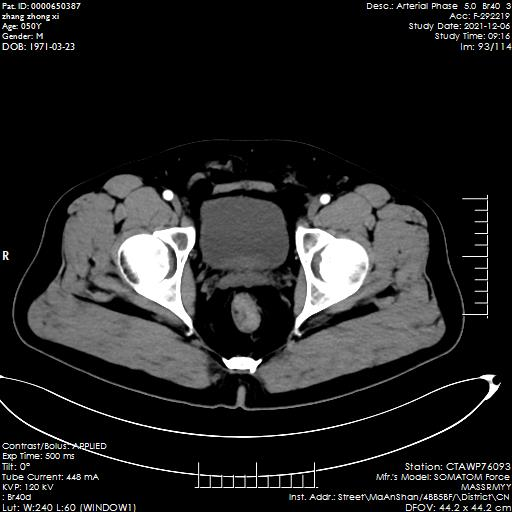

該名男性患者張某,因“大便帶血半年余”入院,在外院做腸鏡檢查提示距肛門(mén)5cm見(jiàn)直徑約3cm不規(guī)則黏連隆起性病變,表面充血污穢,質(zhì)脆,觸之易出血。病理化驗(yàn)結(jié)果提示為腸粘膜高級(jí)別上皮內(nèi)瘤變,局部癌變。入院后,胃腸外科團(tuán)隊(duì)積極完善相關(guān)術(shù)前檢查,經(jīng)過(guò)全科病例討論和充分的術(shù)前準(zhǔn)備,給予行“腹腔鏡下直腸癌根治術(shù)+超低位吻合術(shù)”,手術(shù)過(guò)程順利,術(shù)后予以積極治療,患者恢復(fù)良好。